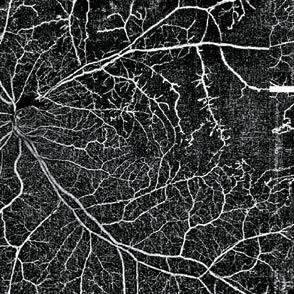

Ilustración Portada: Walter Muñoz

Ilustración basada en el artículo: Tratamiento de la retinopatía diabética proliferativa

Figura 1. Imágenes de un paciente varón de unos 30 años con diabetes tipo 2 mal controlada (hemoglobina A1c >12%) y sin atención ocular previa. La angiografía con fluoresceína en la cita inicial mostró áreas extensas de ausencia de perfusión periférica con frondas de neovascularización (se muestra el ojo izquierdo). La OCT mostró edema macular diabético grave que afecta al centro (arriba, a la derecha) que respondió bien a las inyecciones intravítreas de anti-VEGF (aflibercept) (abajo, a la derecha). Un año después de la presentación, tenía 20/20 en ambos ojos con una A1c <7% debido a una mejor adhesión al cuidado de la diabetes y un mejor control sistémico de la glucosa.  Foto. Ian C. Han, MD.